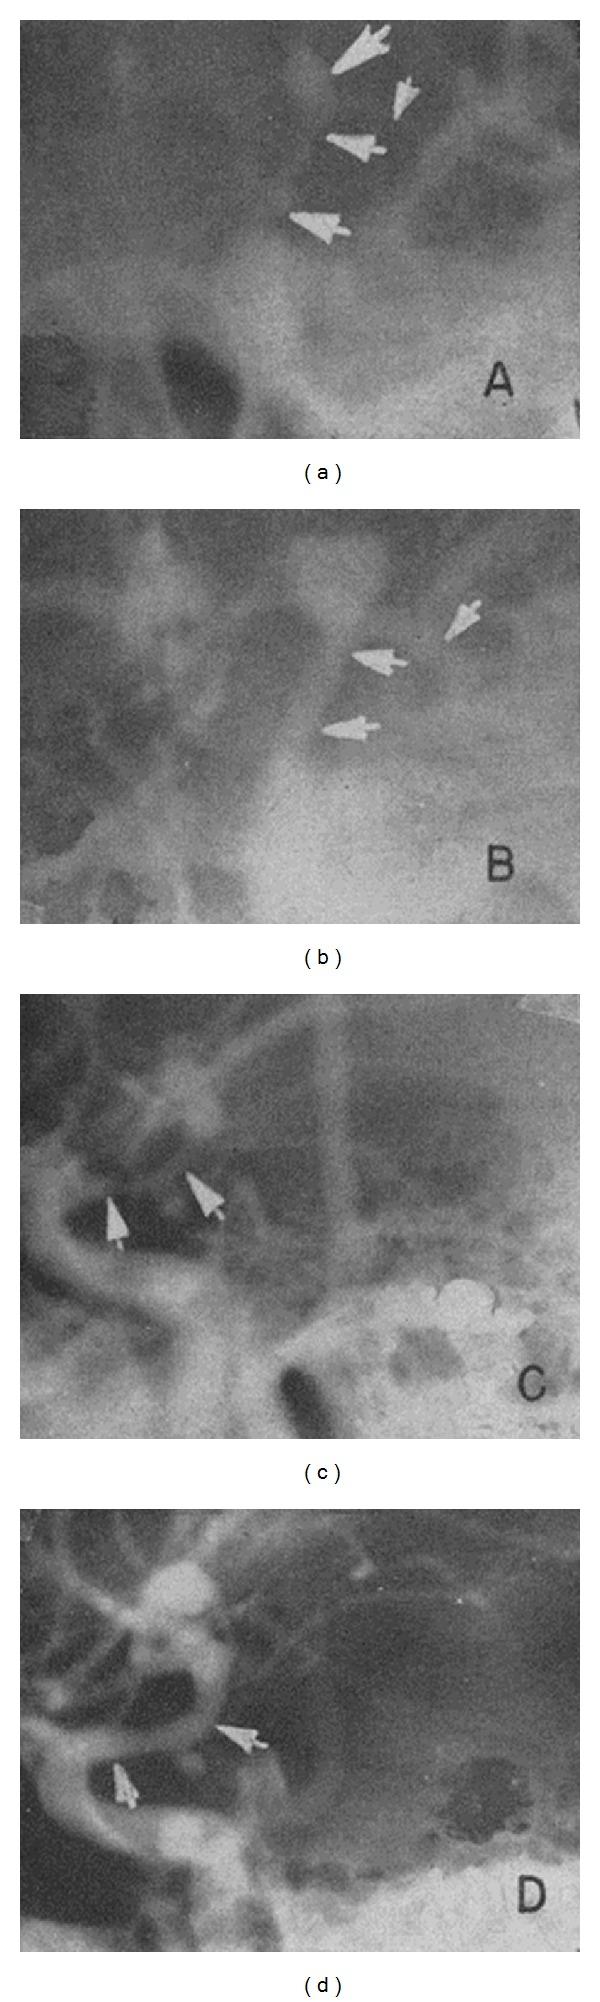

The pathophysiology of cerebral vasospasm following aneurysmal subarachnoid hemorrhage (SAH) is complex and is not entirely understood. Mechanistic insights have been gained through advances in the capabilities of diagnostic imaging. Core techniques have focused on the assessment of vessel caliber, tissue metabolism, and/or regional perfusion parameters. Advances in imaging have provided clinicians with a multifaceted approach to assist in the detection of cerebral vasospasm and the diagnosis of delayed ischemic neurologic deficits (DIND). However, a single test or algorithm with broad efficacy remains elusive. This paper examines both anatomical and physiological imaging modalities applicable to post-SAH vasospasm and offers a historical background. We consider cerebral blood flow velocities measured by Transcranial Doppler Ultrasonography (TCD). Structural imaging techniques, including catheter-based Digital Subtraction Angiography (DSA), CT Angiography (CTA), and MR Angiography (MRA), are reviewed. We examine physiologic assessment by PET, HMPAO SPECT, (133)Xe Clearance, Xenon-Enhanced CT (Xe/CT), Perfusion CT (PCT), and Diffusion-Weighted/MR Perfusion Imaging. Comparative advantages and limitations are discussed.

动脉瘤性蛛网膜下腔出血(SAH)后脑血管痉挛的病理生理学很复杂,尚未完全明确。通过诊断成像技术能力的进步,已获得了一些机制方面的见解。核心技术集中于血管管径、组织代谢和/或区域灌注参数的评估。成像技术的进步为临床医生提供了一种多方面的方法,以协助检测脑血管痉挛和诊断延迟性缺血性神经功能缺损(DIND)。然而,一种具有广泛疗效的单一检测方法或算法仍然难以找到。本文研究了适用于SAH后血管痉挛的解剖学和生理学成像方式,并提供了历史背景。我们考虑经颅多普勒超声(TCD)测量的脑血流速度。对包括基于导管的数字减影血管造影(DSA)、CT血管造影(CTA)和磁共振血管造影(MRA)在内的结构成像技术进行了综述。我们研究了通过PET、HMPAO SPECT、(133)Xe清除率、氙增强CT(Xe/CT)、灌注CT(PCT)以及扩散加权/磁共振灌注成像进行的生理学评估。讨论了它们各自的比较优势和局限性。